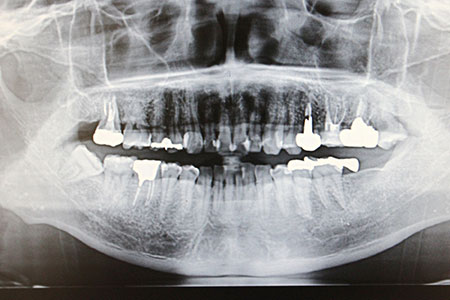

すべての歯を失った、総入れ歯が合わずにお悩みの方へ、従来は8~14本のインプラントが必要でしたが、オールオン4なら最小4本のインプラントで12本の噛める歯をしっかり支えられます。

骨の硬い部分を正確に狙い、角度や力を調整してインプラントを埋入。器具の長さや太さも最適化し、安定した咬合を実現します。オールオン4は高度な技術が必要なため、対応できる歯科医師や医院は限られています。

オールオン4とはたった4本のインプラントで12本の歯を保持する方法です。全ての歯を失ってしまった方、総入れ歯の方に行う治療法です。抜歯からインプラントの埋入、仮歯を入れるまでが1日でできます。

オールオン4はインプラント治療の一種で、外科手術を伴う方法です。そのため、重度の全身疾患がある方などは適応できない場合があります。手術前にはCT撮影や血液検査などを行い、適応の可否をしっかりと確認してから治療を進めます。